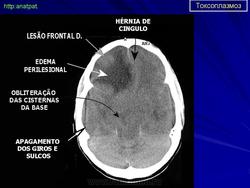

Церебральный токсоплазмоз.

Церебральный токсоплазмоз

Neurotoxoplasmosis

Дифференциальная диагностика изображения